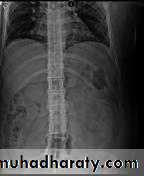

In advanced disease, ossification of the anterior longitudinal ligament and facet joint fusion may also be visible. The combination of these features may result in the typical ‘bamboo’ spine.

Erosive changes may be seen in the symphysis pubis, the ischial tuberosities and peripheral joints.

Osteoporosis and atlantoaxial dislocation can occur as late features.